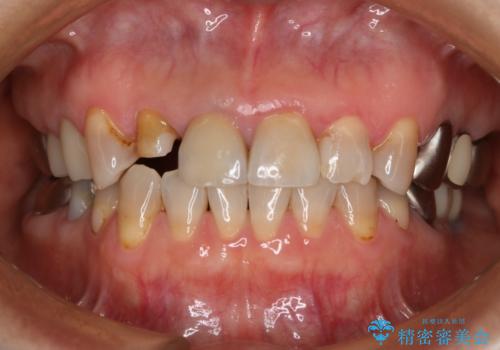

- 右上2番の審美性改善を主訴に来院された患者様です。

切削量と前歯ということからオールセラミッククラウンでの治療を選択しました。